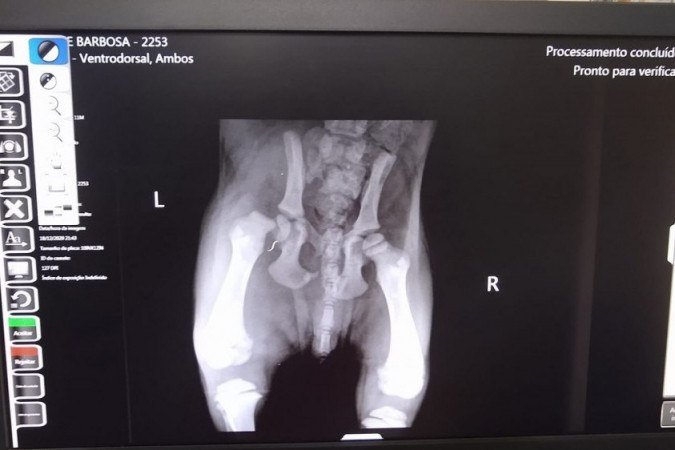

No quartel o labrador recebeu os primeiros atendimentos e foi alimentado com ração. Em seguida, após acionarem uma rede de apoio, os bombeiros o encaminharam para uma clínica veterinária, onde ele passará por uma cirurgia para tratar uma fratura de fêmur.

Bombeiros socorrem filhote atropelado em Taguatinga Foto: CBMDF/Divulgação